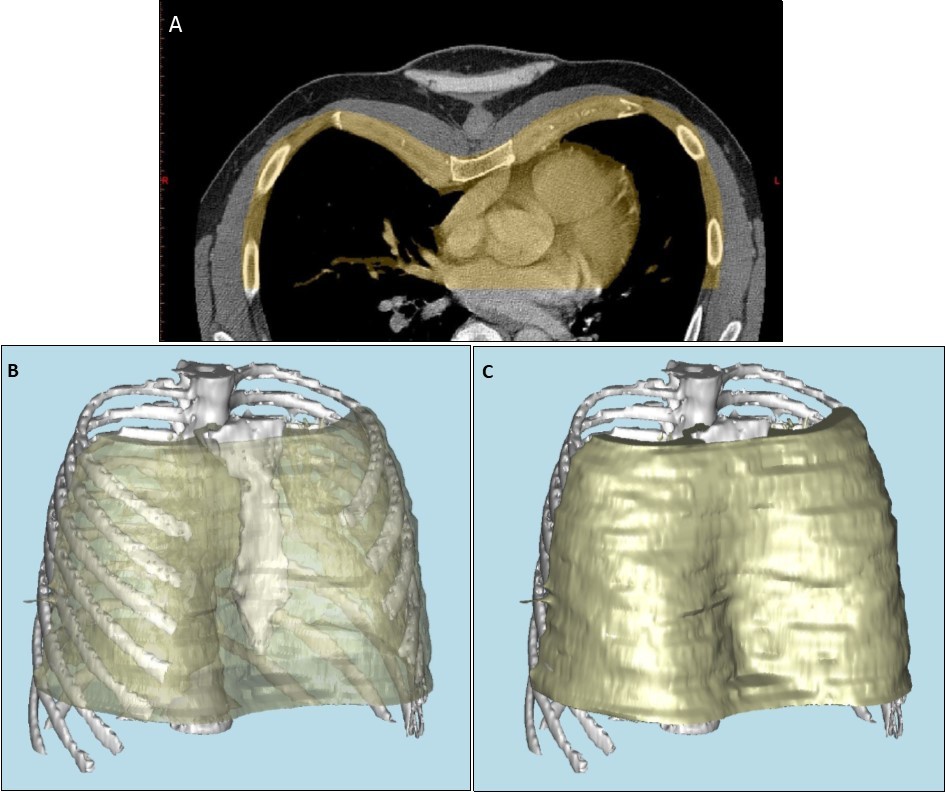

Patients referred for consideration of custom-made chest wall implant underwent an initial consultation with the prosthetists. Three-dimensional computed tomography (3D CT) was performed to assess the skeletal features of the chest wall, using Materialise Mimics software (Materialise, Leuven, Belgium) (Figure 1 a, b, c). A model of the bone structure was then created using a 3D printer, Objet Eden 260vs (Stratasys, Eden Prairie, MN, USA). Alginate was poured onto the 3D model to create an alginate impression (Alginate Colour, DE Healthcare Ltd, Kingthorpe, UK), and a plaster model of the chest wall created from this alginate impression. In lean patients with pectus excavatum, or in Poland syndrome with soft tissue deformity alone, an alginate impression of the whole chest was taken without CT, and the plaster model of the chest created from this. Once a plaster or 3D-printed model was available, a wax prototype of the prosthesis was manually crafted on the plaster model, using carving tools and a blowtorch.

Figure 1.a) Anterior portion of axial computed tomography image of thorax, demonstrating pectus excavatum, with portion used for reconstruction highlighted in yellow. b) and c) three dimensional computer-aided reconstruction of the chest wall model.